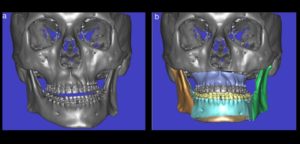

041 – Planificación y Tratamiento en Rehabilitación Oral con Prótesis sobre Implantes usando Análisis Cefalométrico

En los pacientes desdentados, que requieren una prótesis completa ya sea convencional o implanto soportada, los dientes artificiales se colocan en la prótesis completa por